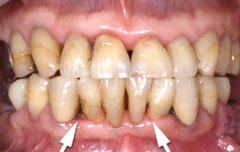

初期の歯周病の治療

| 歯茎にプラーク(歯垢着が)と歯石の沈認められます。歯肉が腫れ、出血がありました。 | 歯科衛生士の治療と、ブラッシング技術の向上により、歯茎が引き締まり健康的な状態になりました。 | |